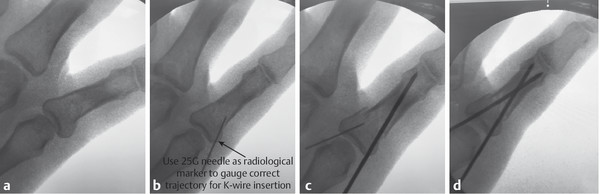

14.4 Kirschner Wire Fixation

Percutaneous K-wire fixation should be considered in many closed hand fracture configurations, where a satisfactory closed reduction has been achieved, but is unlikely to be maintained with splints or casts alone (Fig. 14‑7). However, K-wiring is not always easy to perform and sometimes multiple passes are made in error. To minimize problems, a number of simple steps can be performed.

One must mark the joints with a pen to help with the 3D understanding of the fracture. Radiologic markers such as a 25-gauge orange needle can help guide the trajectory of the K-wire (Fig. 14‑8, Fig. 14‑9). However, when passing the K-wire one should go by feeling the resistance of the cortical bone. Furthermore, making small stab incisions through the skin with a 15 blade is useful rather than stabbing the K-wire through the skin inadvertently catching the extensor mechanism. If repeated attempts are made during surgery, a new K-wire should be loaded on the driver. Repeated attempts and high revolutions should be avoided as thermal damage to bone can result in problems with union and infection.